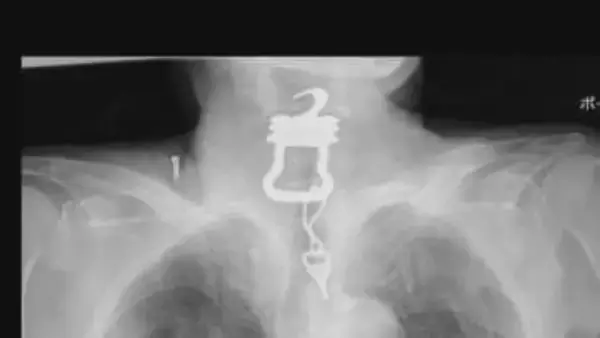

2022年、大阪市内の病院に入院していた男性(当時82)の喉から12センチの「カギ」が見つかりその後...